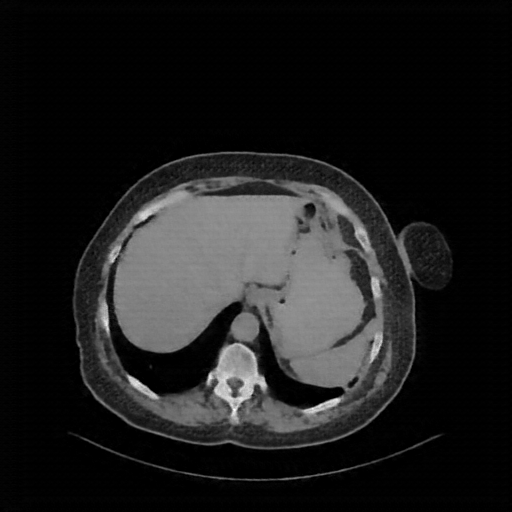

Generated VENOUS CT scan (A→B translation)

Full window (WL 1023.5, WW 4095 β†’ Low βˆ’1024, High +3071)

Actual HU range: [-1024.0, 1032.9]

Mediastinum window (WL 40, WW 400 β†’ Low βˆ’160, High +240)

Actual HU range: [-160.0, 240.0]